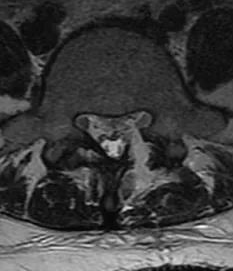

术中摘除突出髓核后的镜下表现